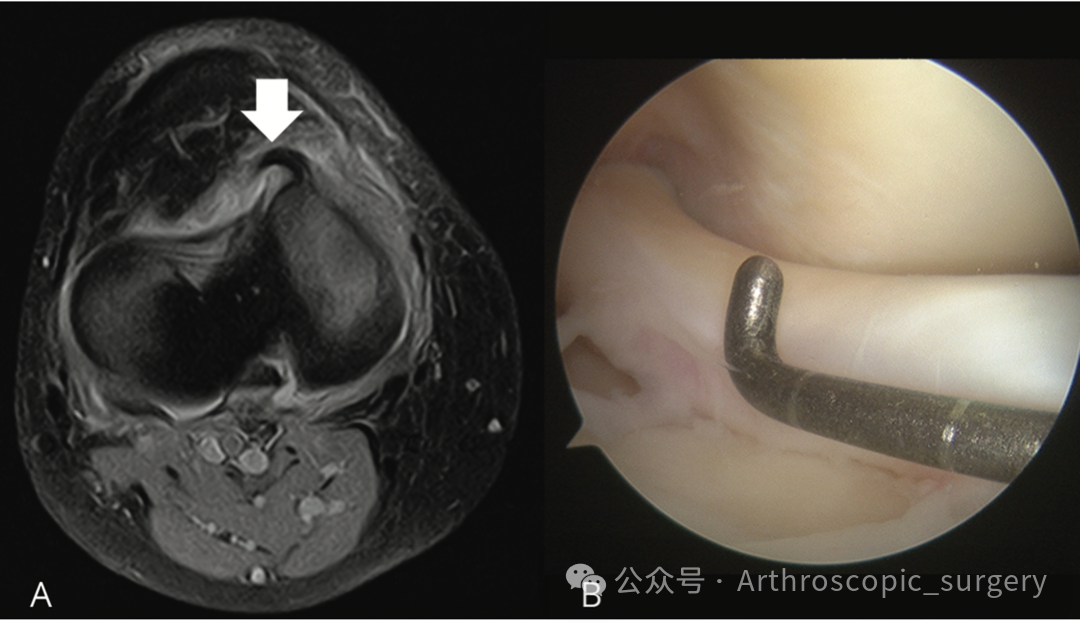

除了上述经典征象,Arth君今天要特别介绍一种在横断面图像上的新发现——水牛角征(Buffalo Horn Sign)。

具体表现为:内侧半月板在内侧胫骨平台前缘突出的低信号区域,形似一只“角”。外侧半月板在连续两层横断面图像上,表现为与外侧胫骨平台前缘平行的低信号角状带。

这个征象是由于移位的半月板“柄”部被横断面切面切到而形成的。研究显示,它的敏感度约为46.4%,是继髁间窝片段征和领结征消失之后的第三大常见征象。

因为它非常容易识别,且具有高度特异性——在正常的半月板中从未发现过此征象。识别它对于制定手术计划、决定是否进行半月板修复至关重要。

桶柄样撕裂是膝关节的“紧急状况”,及时的诊断能为半月板缝合创造机会。

咱们不仅要学会看矢状面的“双PCL”,也要关注横断面上的“水牛角(Buffalo Horn Sign)”。